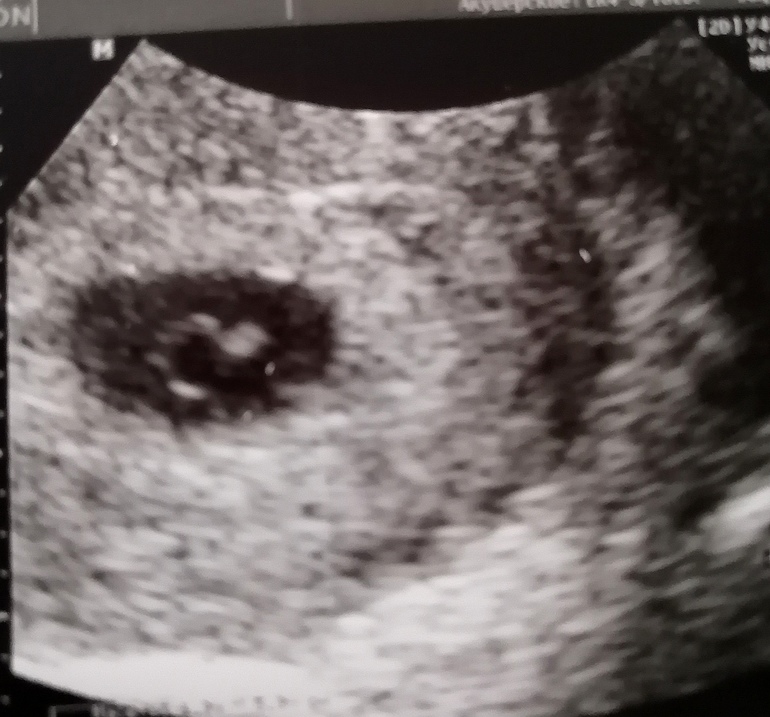

Сходила на УЗИ 🥰

Не выдержала я неделю, пошла сегодня, и не зря 🤗

По М срок 6,2 по УЗИ так же)))

Нашли сб ❤️

Спасибо! Делали двумя способами.

Фото с трансвагинального.